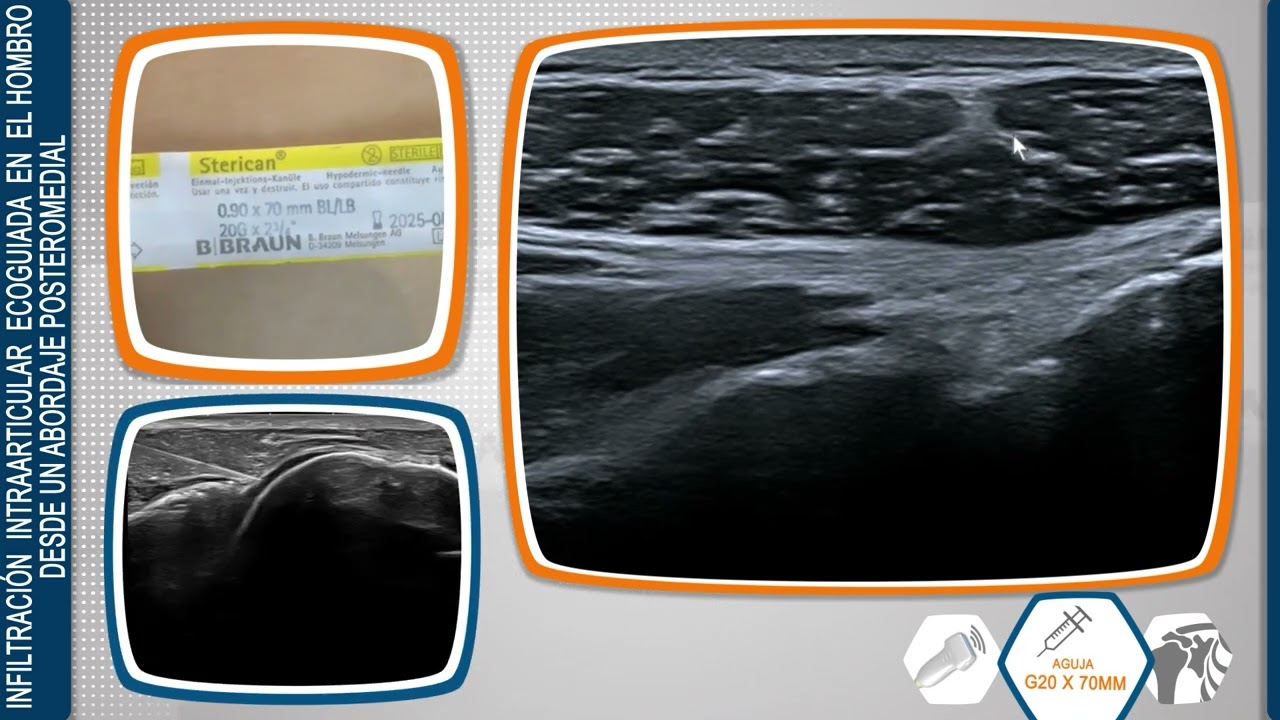

´Técnica de Infiltración Intraarticular Ecoguiada en el Hombro